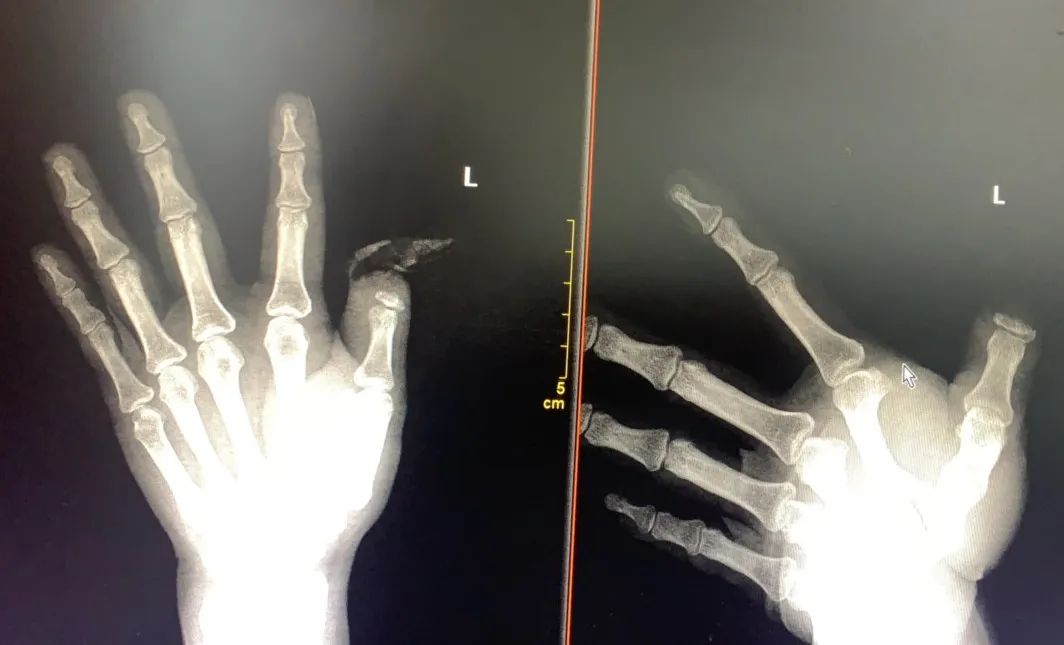

经详细的相关检查后,见「大拇指的肌腱自肌腹抽出约 20 多厘米、血管神经等均撕脱损毁严重、组织损伤严重」,当即诊断为「左拇指旋转撕脱性完全离断伤」,其「拇指被高速旋转机械缠绕和强力牵拉而造成离断」是此类损伤的特点,因此,《手足外科学》及《手外科手术学》等将该类断指作为特殊类型的断指再植,其损伤程度及手术难度远远高于一般的再植,且成活率低,除了需要精湛的血管吻合技术外,还需要精通血管神经肌腱撕脱损毁后的移位及转位修复技术。